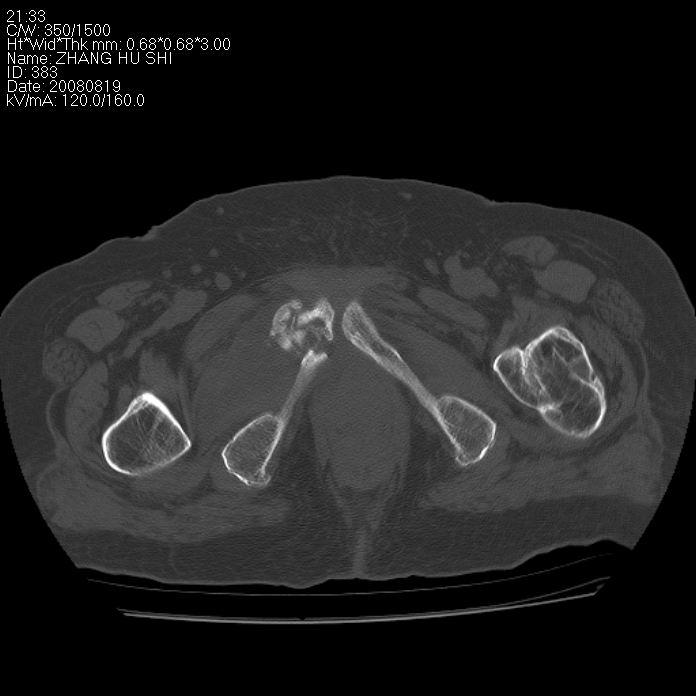

标题: CT15287:女 93岁 右髋关节疼痛 原左侧粗隆间骨折 CT发现右耻 [打印本页]

标题: CT15287:女 93岁 右髋关节疼痛 原左侧粗隆间骨折 CT发现右耻

支持转移并周围软组织侵犯右闭孔内肌侵犯,但tb不能完全除外。

耻骨软骨肉瘤可能性大